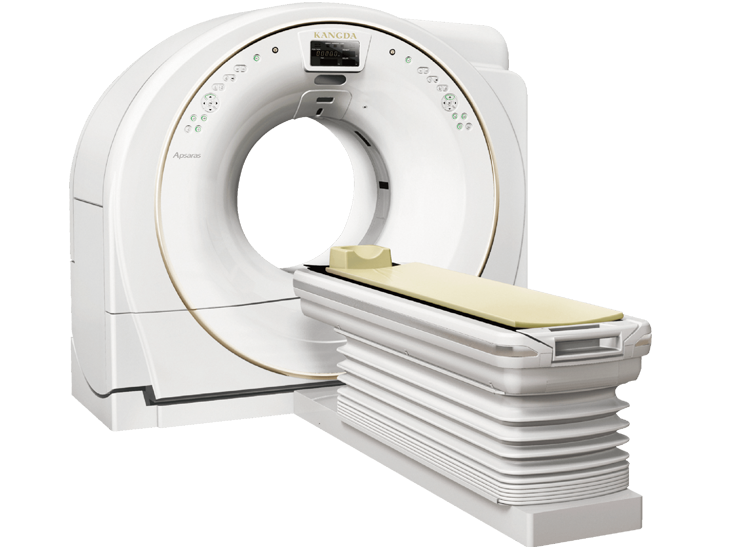

Scanner Gantry

广视野扫描架

采用了最先进的驱动技术,极大的提高了信号的传输效率,确保进行快速的扫描。 机架采用标准几何设计,射线扇形角小。 机架上横断位,矢状位,冠状位三个方向定位灯,确保定位的快速准确。 采用呵护患者的先进设计,机架开口径达 750mm。